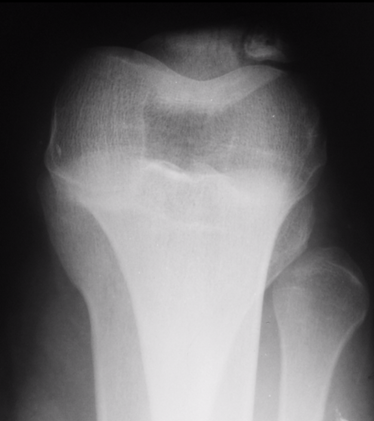

Juvenile Osteochondritis Dessicans

Despite the nomenclature, the disease process is related to bone delamination and necrosis rather than cartilaginous injury or disease. Lateral aspect of the medial condyle of the femur is the most common site. This condition is not unique to athletes. Plain radiographs are indicated if the condition is suspected, as the lesion will be demonstrated as an area of lucency on x-ray. MRI may be obtained to assess for additional injury, as well as more detailed evaluation of the chondral lesion. However, this may be more useful in adults as compared to children and adolescents.9 The criteria for use in children have not yet been well defined, and adult criteria may not be applicable.10 Patients often present with anterior or medial knee pain. There may be small effusion on exam and often, but not always, tenderness to palpation of the femoral condyle. If a lesion is visualized, rest and activity restriction is the approach of choice and typically leads to spontaneous resolution in 8-12 weeks in children. The patient should be pain free, and x-ray should demonstrate healing. Spontaneous resolution is more common in children and adolescents than in adults. Knee immobilization can be indicated in severe cases as can surgical intervention for unstable versions.9 Stable lesions without adequate healing in 3-6 months warrant evaluation by an orthopedic surgeon for possible operative intervention.11

Case courtesy of Dr. Maulik S. Patel, Radiopaedia.org. From the case rID: 10668